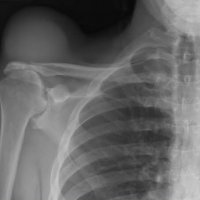

The geyser sign is a subcutaneous pseudotumor above the acromioclavicular joint, also known as AC joint cyst. The geyser sign is an infrequently encountered imaging sign that was originally described on conventional fluoroscopy-guided shoulder arthrography. The first case report of these cysts occuring in association with rotator cuff tears was made by Dr. Edward Craig in 1984, and again in 1986. The sign derives its name from its geyser-like appearance.

On physical examination, an AC joint cyst is a palpable fluid-filled mass. MRI scanning or a shoulder arthrogram should be obtained to evaluate the shoulder. Unenhanced MRI scans showing a large rotator cuff tear, a degenerated AC joint, and a large subcutaneous cyst adjacent to the AC joint is virtually patognomonic for the disease. Contrast administration on MR arthrogram will show the synovial fluid or intra-articular contrast extravasates from the glenohumeral joint into the subacromial bursa, into the AC joint, and then into an overlying cystic mass when a full-thickness rotator cuff tear is present, resembling a geyser spouting upwards.